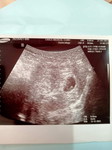

14สัปดาห์

แม่มีเลือดออกทางช่องคลอด ไปพบคุณหมอเมื่อวาน หมอบอกว่าคุณแม่มีภาวะเสี่ยงแท้งคุกคาม อัลตราซาวด์ลูกยังอยู่ หัวใจเต้นปกติ แม่บ้านไหนเป็นบ้างค่ะ แล้วดูแล้วตัวเองกันยังไงกันบ้าง